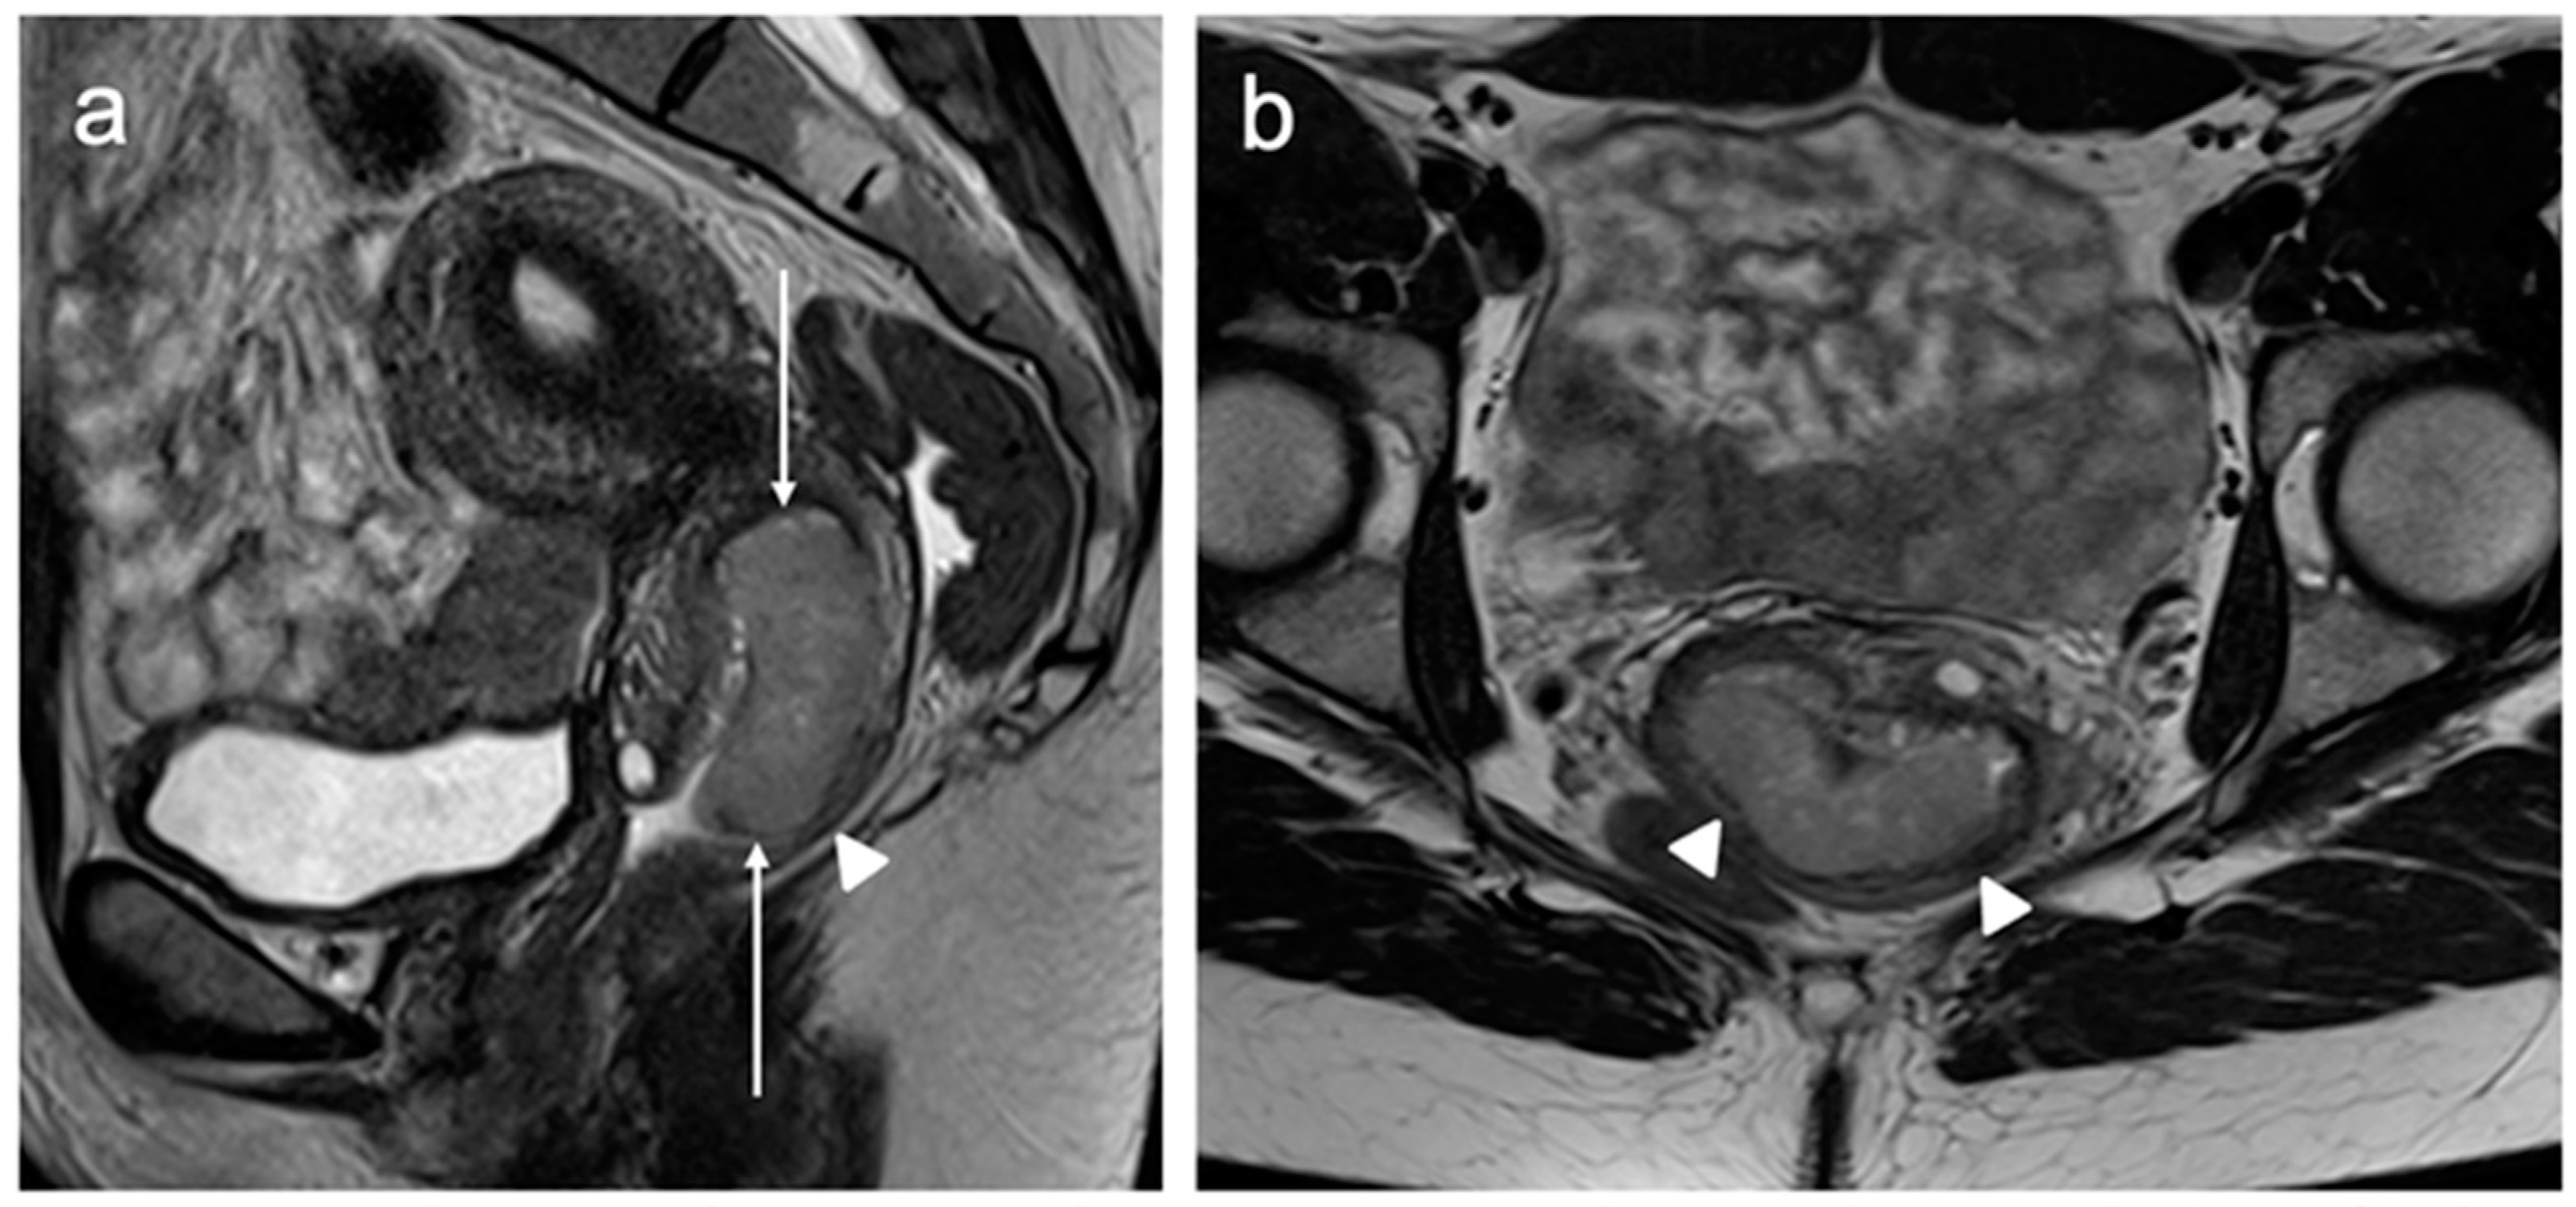

| Stage III | Involves the lower third of the vagina and/or extends to the pelvic wall and/or causes hydronephrosis or non-functioning kidney and/or involves pelvic and/or paraaortic lymph nodes |

| IIIB | Extension to the pelvic wall and/or hydronephrosis or non-functioning kidney (unless known to be due to another cause) |

| IIIC | Involvement of pelvic and/or paraaortic lymph nodes |

| IIIC1 | Pelvic lymph node metastasis only |

| IIIC2 | Paraaortic lymph node metastasis |